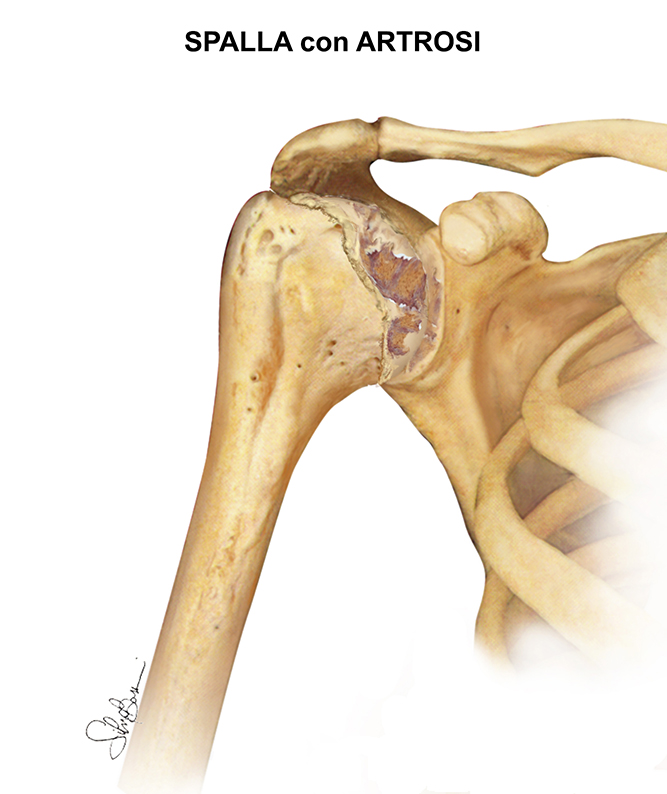

- Osteoartrosi (malattia degenerativa articolare): Si tratta di un tipo di artrite "usurante" legato all'età. Di solito si verifica negli ultra-cinquantenni, ma in rari casi si può riscontrare anche in soggetti più giovani. È causata da un progressivo assottigliamento della cartilagine articolare la quale non riuscendo più a lavorare come “ammortizzatore articolare” permette lo sfregamento dei capi ossei l’uno contro. In questo modo, con il passare del tempo, l'articolazione diventa progressivamente rigida e dolorosa.